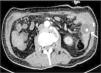

Los datos macroscópicos de isquemia intestinal observados durante la laparotomía, se resolvieron inmediatamente después del retiro del catéter y liberación manual de la intususcepción intestinal. Por este motivo, se optó por no resecar el segmento de intestino involucrado (fig. 3). Posteriormente, se le realizó al paciente una endoscopia, durante la cual se observaron 2 úlceras en la segunda porción del duodeno, posiblemente relacionadas con la migración del catéter. Se colocó una sonda GEP 24Fr mediante técnica de arrastre (PULL) (fig. 4). Se inició terapia estándar con inhibidor de la bomba de protones para cicatrización de las úlceras. En su visita de seguimiento más reciente, 7 meses tras la recolocación GEP, el paciente presentó falla en la prueba de deglución de líquidos, por lo que requirió una combinación de dieta oral y alimentación por sonda GEP. El paciente, al momento de la redacción del presente reporte, continuaba con ejercicios de rehabilitación de la deglución y fisioterapia.